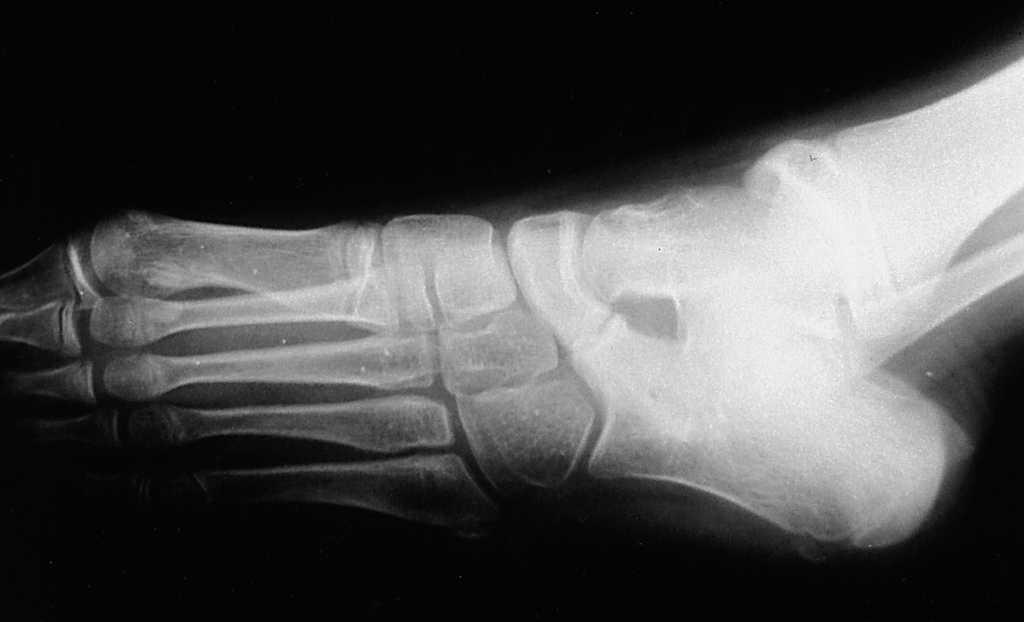

En la mayoría de las sinóstosis C-E se llegó al diagnóstico mediante una radiografía del pie en proyección oblicua (proyección de Sloman) (fig. 1) y pocas veces se precisó de una TAC. Por el contrario, la exploración radiográfica de las sinóstosis A-C sólo permitió, en algunos casos, sospechar una sinóstosis ante la poca definición de la articulación media astrágalo-calcánea, la presencia de un pico dorsal en la cabeza del astrágalo, o la aparición de una imagen en C, pero para concretar el diagnóstico se precisó siempre de una exploración por TAC (fig. 2).

Figura 1. Proyección radiográfica oblicua de un pie con una sinóstosis calcáneo-escafoidea, que muestra una zona intermedia cartilaginosa.